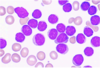

En 39-årig fik pludselig opstået hovedpine. Ved objektiv undersøgelse findes ingen neurologiske udfaldssymptomer eller organomegali. En fæcesprøve er positiv for okkult blod. Der fremkommer områder med kutan purpura på ekstremiteterne. Blodprøver viser Hb på 5,9 mmol/l, hæmatokrit på 29 %, trombocyttal på 29 x 109/l (150-450), og leukocyttal på 75 x 109/l. Udstrygning af perifert blod ser ud som vist nedenfor, og der er desuden schistocytter. Plasma D dimer, trombintid og APTT er alle forhøjede.

*d. t(15;17)

Note: t(15;17) giver akut promyelocytleukæmi (APL), som er en subtype af AML. Klassisk er:

- kutan purpura

- anæmi

- epistaxis

- forhøjet APTT

- leukocytal >10 mia/l

- svær trombocytopeni

- forhøjet D-dimer

- forhøjet APTT*

- Når man har et trombocyttal på under 30-40 mil/L så skal man mistænke APL. Dette lave tal giver selvfølgelig anledning til kurtan purpura og epistaxis.*

- Schistocytter har vi lært er der ved TTP. De er der åbenbart også ved APL.*